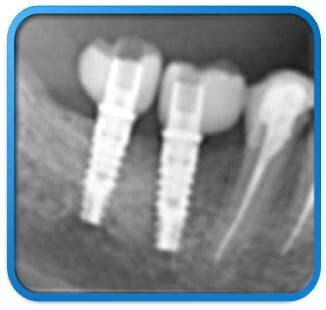

Figg. 15, 16_Controllo radiografico post-implantare e follow-up ad 1 anno.